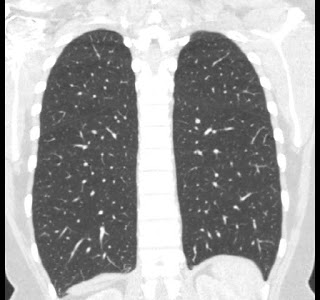

40 year old female. Breast implants 17 years ago, most likely Dow Corning. Symptoms from upper body for 6-7 years. Pain in breasts, ribs, back, neck. Skin rash. Headache and dizziness, weakness, numbness and vision disturbing. Sudden sleep episodes. Painful lymph-notes. These images are from 2010 and diagnose results were "No findings". Patient is scheduled for explantation in mid Feb. 2012